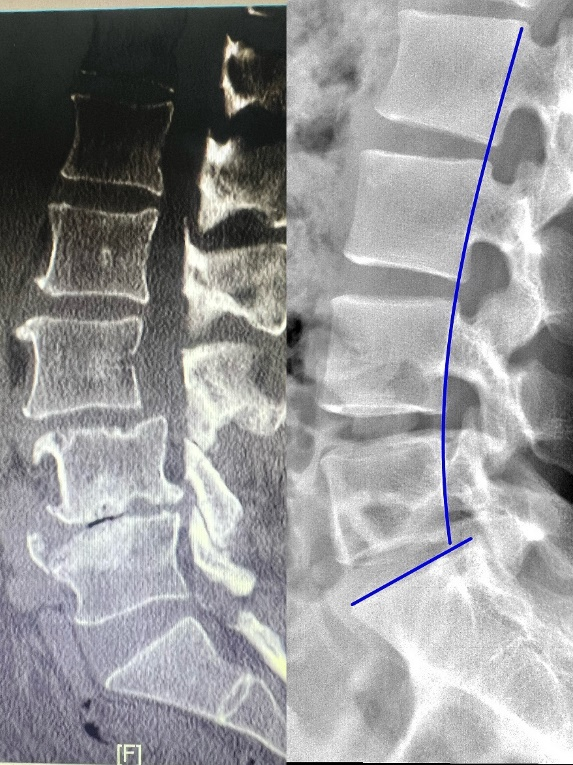

经熟人介绍,林大爷找到协和医院旗山院区骨科王振宇副主任医师。完善检查发现,林大爷腰椎出现严重的多节段滑脱和侧弯畸形,并压迫神经。同时,由于长期受力不平衡导致林大爷骨质严重硬化,这大大增加了术中可能损伤神经的风险,手术难度高。

▲与右侧正常脊柱图比较,林大爷的腰椎滑脱畸形严重